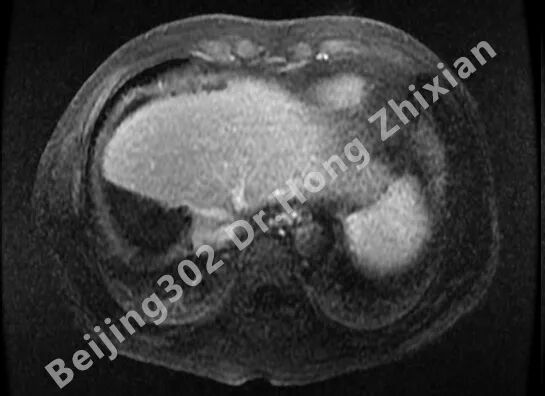

病例简介